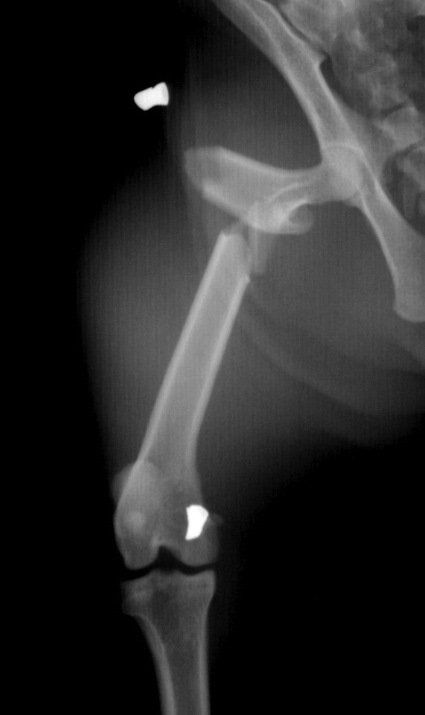

- reconstructive surgeries during broken bones limbs with the use of pins, plates and screws.